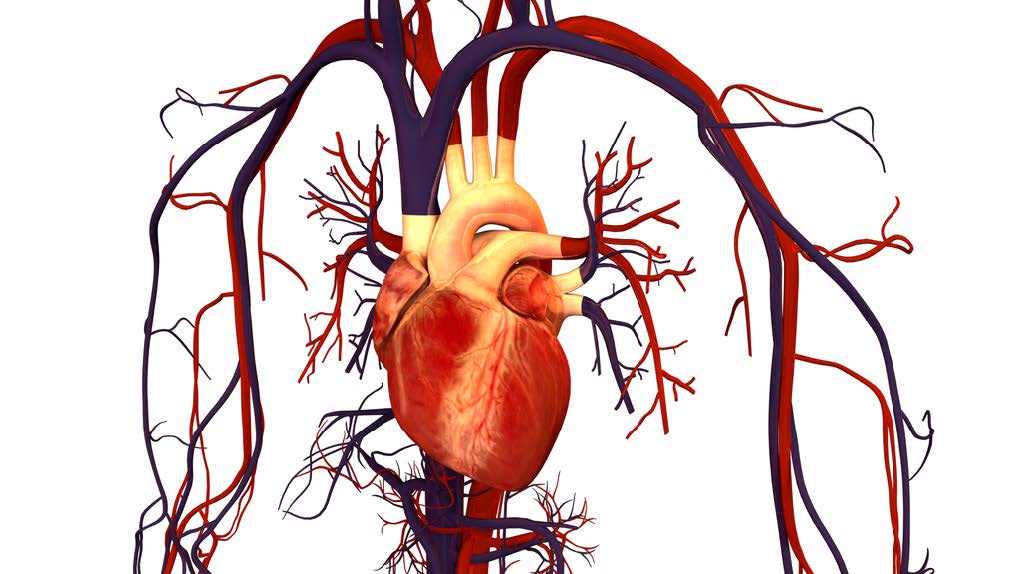

Before looking at the electrophysiology of the heart, let’s review the basic cardiac anatomy. The adult heart is approximately the size of your fist and sits in the left side of the thoracic cavity in front the lungs. The heart is orientated in the chest rotated at about 30 degrees to the left lateral side (Kaelber, 2013). The heart is a mechanical pump driven by electrical activity.

The two atria are the smaller chambers and the two ventricles are the larger chambers of the heart. The right ventricle is the most anterior structure of the heart. The left ventricle is generally twice as thick as the right ventricle due to the force it has to generate to push blood through our lungs.

Under normal conditions the valves ensure that the blood only flows in one direction through the heart. De-oxygenated blood returns to the right side of the heart via the venous circulation. It is pumped into the right ventricle and then to the lungs where carbon dioxide is released and oxygen is absorbed. Oxygenated blood from the lungs returns to the left side of the heart into the left atria, then into the left ventricle from where it is pumped into the aorta and arterial circulation. Blood travels from right side to left side via the lungs only. However, the chambers themselves work together. The two atria contract simultaneously, and the two ventricles contract simultaneously.